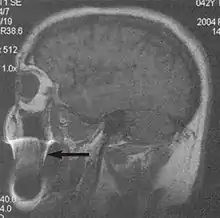

Fig. 8. Gibbs artifact (T1 sagittal study of the brain).[1]

Gibbs artifacts or Gibbs ringing artifacts, also known as truncation artifacts are caused by the under-sampling of high spatial frequencies at sharp boundaries in the image.[5][6] Lack of appropriate high-frequency components leads to an oscillation at a sharp transition known as a ringing artifact. It appears as multiple, regularly spaced parallel bands of alternating bright and dark signal that slowly fade with distance (Fig. 8). Ringing artifacts are more prominent in smaller digital matrix sizes.[1] Methods employed to correct Gibbs artifact include filtering the k-space data prior to Fourier transform, increasing the matrix size for a given field of view, the Gegenbauer reconstruction and Bayesian approach.[1] ==Machine/hardware-related artifacts== This is a wide and still expanding subject. Only a few common artifacts are recognised.[1]